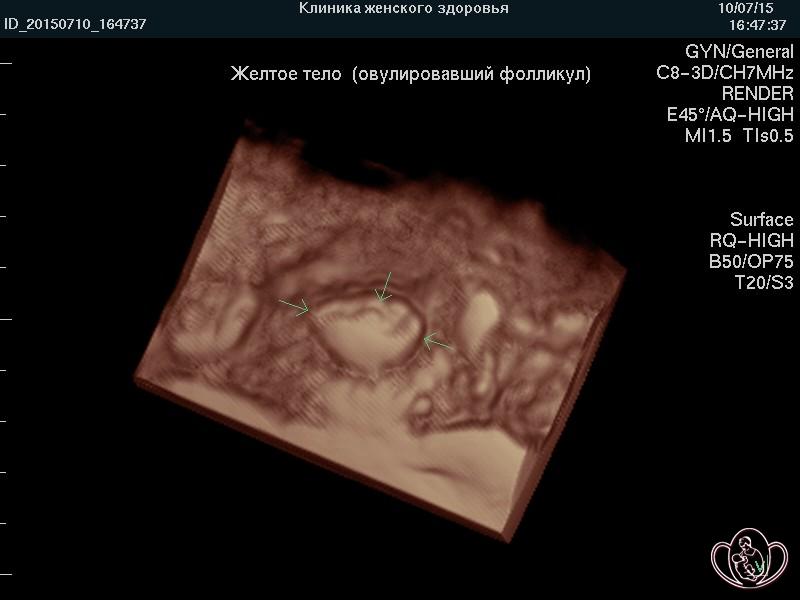

Чтобы определить сосудистую причину (фактор) бесплодия у женщин, в Спа-клинике женского здоровья проводится ультразвуковое исследование в 3D и энергетический допплер с использованием аппаратов экспертного класса.

| 3D фото овуляции: четко очерчены края свежего разрыва (овуляции) фолликула | ![]() |